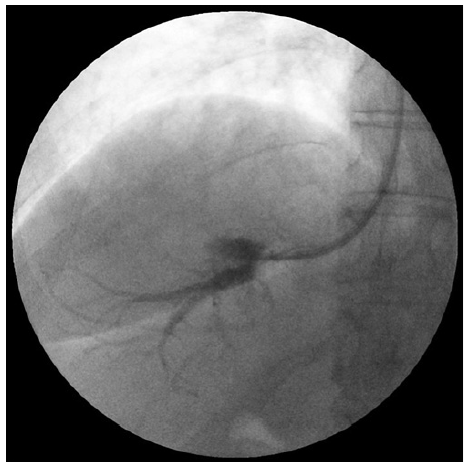

Cardiopulmonary and hepatic hemodynamic (HH) study re-vealed moderate PAH (mean PAP 40 mm Hg, pulmonary capillary wedge pressure 5 mm Hg) and HVPG of 6 mm Hg, which was suggestive of non-clinically significant sinusoidal PHT (shown in Fig. 3). There were no hepatic vein-to-vein communicants detected during the HH study.